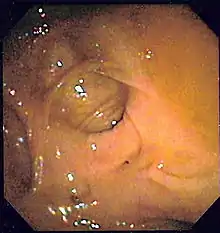

A positive fecal occult blood test | |